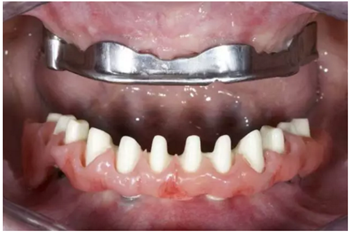

試戴上頜NobelProcera CAD/CAM海德式桿卡(IBO)以及下頜NobelProcera二氧化鋯種植橋(PIB)。

手術(shù)后16周最終修復(fù):上頜覆蓋義齒是卡扣在鈦桿卡(IBO)上,義齒牙冠部分是由二矽酸鋰玻璃陶瓷制作的單冠。下頜的氧化鋯種植長(zhǎng)橋(PIB)上同樣也制作二矽酸鋰玻璃陶瓷的單冠并進(jìn)行粘接。